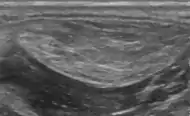

Medical ultrasonography of a lipoma in the thenar eminence: It is hyperechoic compared to adjacent muscle, and relatively well-defined, with miniature hyperechoic lines.[21]